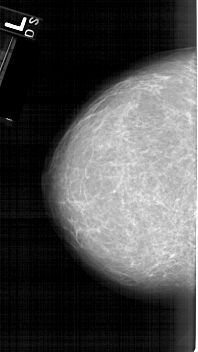

A_1610_1.RIGHT_MLO

LEFT_CC LINES 6331 PIXELS_PER_LINE 3556 BITS_PER_PIXEL 12 RESOLUTION 43.5 NON_OVERLAY